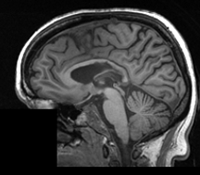

Slicer Registration Library Case #16: Manual alignment of intra-subject Brain MRI

| fixed image/target | moving image |

- fixed: 1mm isotropic;256 x 256 x 146

- moving: 1.2mm isotropic; 256 x 256 x 116